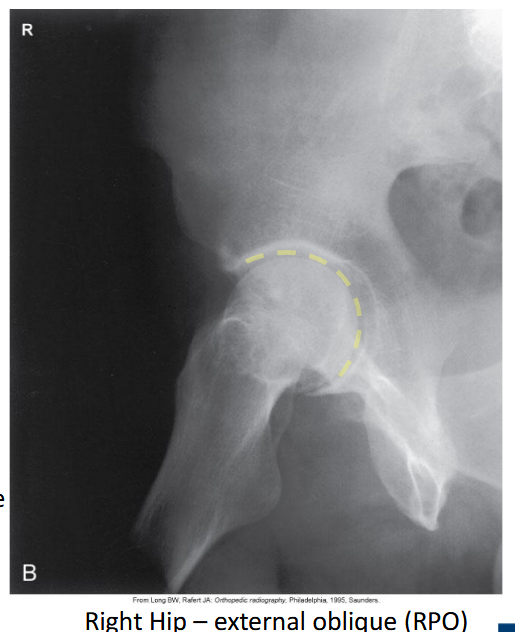

What is the patient position for an external oblique Judet view?

Affected side down 45°.

Which oblique Judet view produces a 'C'-shaped acetabulum?

External oblique.

<p>External oblique.</p>